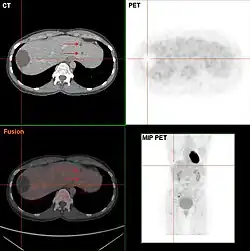

Da eine Leberzyste in den meisten Fällen symptomlos ist, ist sie meist ein Zufallsbefund bei einer Ultraschalluntersuchung. Bei vorhandenen Symptomen oder Komplikationen erfolgt die Diagnose mittels bildgebender Verfahren, meist mittels Ultraschall oder Computertomographie. Dabei können nichtparasitäre von parasitären Leberzysten unterschieden werden.